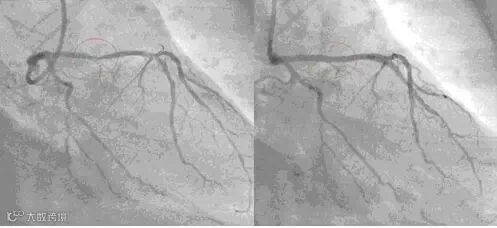

这位Hakim让他自己在家中做一个食疗,他吃了一个月。一个月后他去同一家医院做检查,发现三条血管干干净净,原来堵塞的地方已经全通了。他是一位虔诚的回教徒,为了让更多的人受益,他把自己的经验放在网上分享,他的前后两张血管照片也放了在网上,在照片中,服用食疗之前与之后的分别连普通人也看得出来。